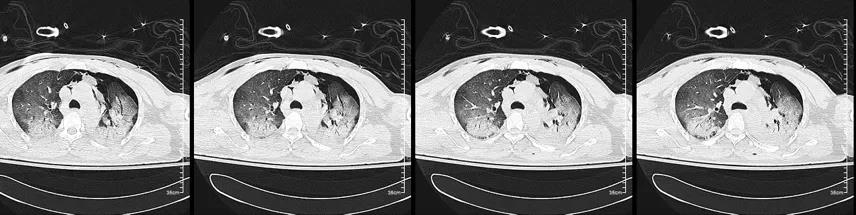

入院时肺部CT(图1):纵隔气肿,皮下气肿,两肺广泛渗出,两下肺实变。

图1. 入院时肺部CT